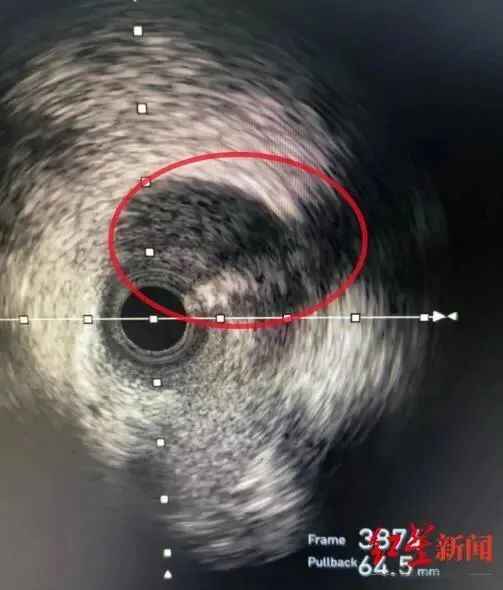

医生经过多项检查,确定了病因——前降支血管夹层影像,俗称自发性冠脉动脉夹层(SCAD)。简单来说,就是血管内壁有撕裂,漏出的血液被尚还完好的血管外壁兜着,犹如自行车胎“鼓包”。